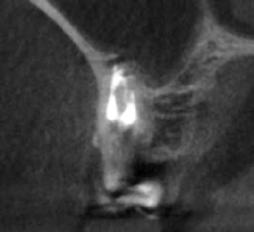

A radiológiai felvételek elemzése során a fog gyökércsúcsának megfelelően radiolucens elváltozást észleltünk, valamint a fognyak területének megfelelően szintén egy radiolucens területet figyelhettünk meg (1–2. ábra). Az elváltozások kiterjedésének és mélységének pontosabb meghatározása érdekében CBCT-felvétel készült (3. ábra). A felvétel alapján Heithersay-féle III. osztályú külső fognyaki gyökérfelszívódást diagnosztizáltunk (Heithersay Class III external cervical invasive root resorption; ECIR). Ezzel egyidejűleg pedig szimptomatikus periapikális periodontitis is fennállt. Ezt követően a pácienst a vizsgálati eredményekről, a kezelési alternatívákról és a várható prognózisról is tájékoztattuk.

A CBCT-felvételek rendkívül hasznos információkkal szolgálhatnak az endodonciai kezelések során. A felvételek segítségével meghatározhatjuk a külső fognyaki rezorptív lézió kiterjedését, felismerhetjük és osztályba sorolhatjuk az esetleges periapikális elváltozásokat, valamint nagyobb pontossággal felmérhetjük a fog belső anatómiai felépítését. Több szerző egymástól függetlenül is igazolta, hogy a CBCT rendkívül hasznos eszköz a rezorptív léziók diagnosztizálása során.

3. a–d ábra: A koronális síkú metszeten jól megfigyelhető a lézió mesio-distalis kiterjedése (a), a szaggitális síkú metszet a lézió vesztibulo-orális nagyságát mutatja (b), a gyökércsúcs körül elhelyezkedő lézió a 3 dimenziós rekonstrukciós képen és a mesio-disztális irányú metszeten is jól megfigyelhető (c–d).

A cikkekben bemutatott esetnél a kezelésre szoruló fog gyökércsúcsánál periapikális lézió volt megfigyelhető és ezzel egyidejűleg külső fognyaki gyökérrezorpció is fennállt. A periapikális és a rezorptív lézió méretének pontos meghatározását és térbeli elhelyezkedésének vizsgálatát CBCT-felvétel segítségével végeztük.

A periapikális léziók rezekciót követő gyógyulási hajlamát több faktor is befolyásolhatja. Ezek közül elsősorban a retrográd preparáció mélységét (amelynek minimum 3 mm-t el kell érnie) és a retrográd gyökértömés során felhasznált anyagot emelnénk ki. A beavatkozás óta eltelt idő is hatással van a gyógyulás aktuálisan megfigyelhető stádiumára. Minél hosszabb idő telt el a beavatkozás óta, potenciálisan annál teljesebb körű csontos telődésre számíthatunk. Ebben az esetben az obszervációs periódus során több CBCT-felvételt is készítettünk, hogy végig tudjuk követni a gyógyulás folyamatát. A kezelés során a fogat szándékosan eltávolítottuk, majd a rezorpciós üregben lévő granulációs szövetet kikürettáltuk és a megtisztított felszíneket 90%-os triklór-ecetsavval fertőtlenítettük. Az így előkészített üreget hidrofil tulajdonságokkal rendelkező dual kötésű nano-hibrid resintartalmú ionomer cementtel töltöttük fel (Geristore, DenMat; 4. ábra).

Ezt követően a gyökércsúcsot extraorálisan rezekáltuk, majd a gyökércsatornát retrográd irányból ultrahangos eszközök segítségével 3 mm mélységben feltágítottuk (EndoSuccess apikális sebészeti készlet, EndoSuccess apical surgery kit; ACTEON). A retrográd gyökértömést ásványi trioxid aggregátum (mineral trioxide aggregate, MTA) felhasználásával végeztük (CeraPutty, Meta Biomed), majd replantáltuk a fogat. A visszahelyezést követően szemi-rigid sín segítségével stabilizáltuk a fogat, amelyet 4 hét elteltével távolítottunk el (5. ábra). A beavatkozásokat követően 6 hónappal a gyógyulás ütemének ellenőrzése érdekében kontroll CBCT-felvételt készítettünk. A felvételen a terület maradéktalan regenerációja volt megfigyelhető, a periapikális lézió szinte teljes mértékben telődött (6. ábra). A szájüregi állapot is megfe-